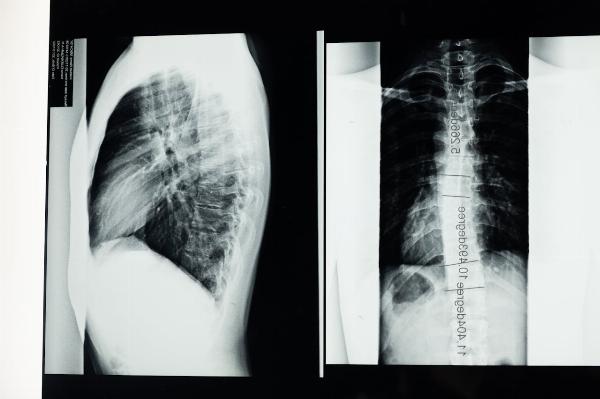

Scoliosis, a condition characterized by an abnormal curvature of the spine, affects millions of people worldwide. While it manifests differently in each individual, common symptoms include uneven shoulders, uneven waist, and sometimes back pain. Understanding the symptoms and treatment options for scoliosis is essential for companies looking to support their employees effectively.

Symptoms & Treatment for Scoliosis: